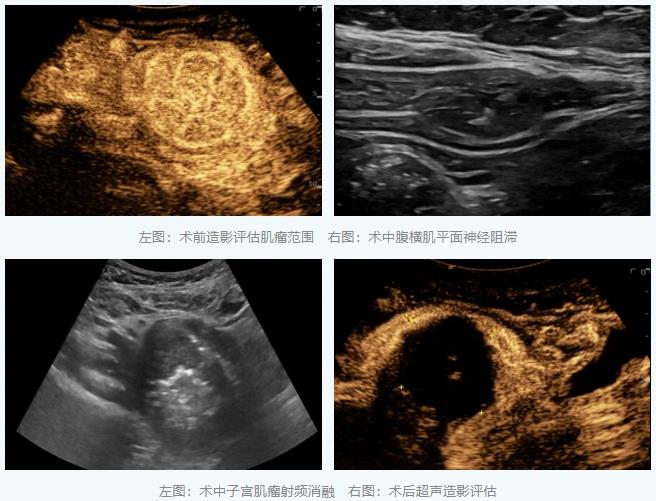

病例二:为巨大子宫肌瘤治疗配上“舒适化治疗”

另一位女性患者因巨大子宫肌瘤(约70×55×55毫米)导致严重经量增多和压迫症状。此类肌瘤消融时间较长,单纯局麻术中疼痛明显。为提升治疗体验,团队创新性地采用了“超声引导下腹横肌平面神经阻滞联合局部浸润麻醉”的方案。

在超声直视下,李彦青主任医师将麻醉药物精准注射到支配手术区域的神经周围,实现了高效的区域镇痛。在整个长达40多分钟的消融过程中,患者生命体征平稳,无明显痛感,第二天出院。这种麻醉方式避免了全身麻醉的风险,显著减轻了术后疼痛,减少了镇痛药用量,真正体现了“以患者为中心”的舒适化医疗理念。